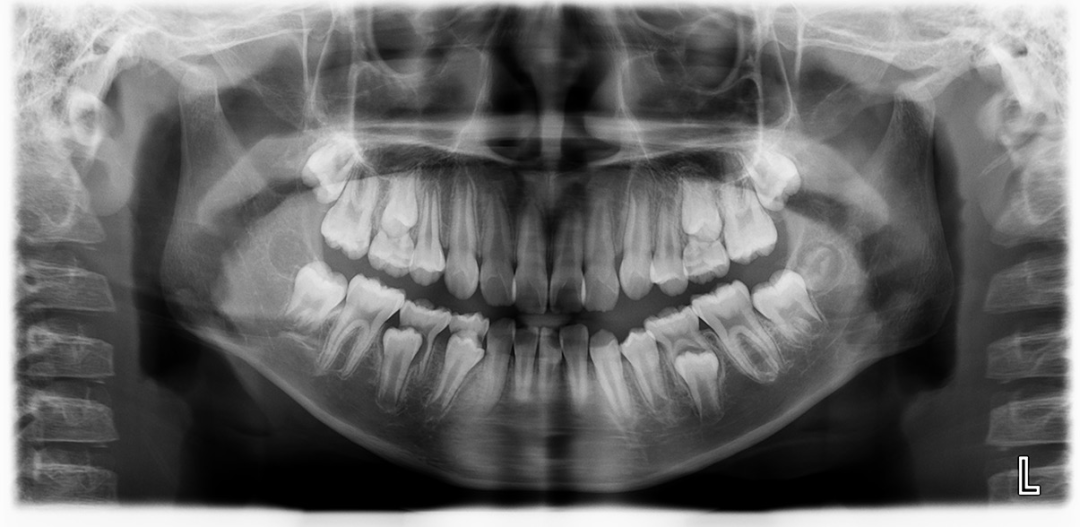

就像这位小朋友主诉嘴突、没下巴,牙齿拥挤,家长带孩子来也是希望能通过不拔牙矫正改善好孩子的牙齿情况。

考虑到孩子面型上颌突,下颌后缩,牙齿矫正不拔牙排齐牙齿,调整牙齿咬合,内收前牙,引导下颌前伸。